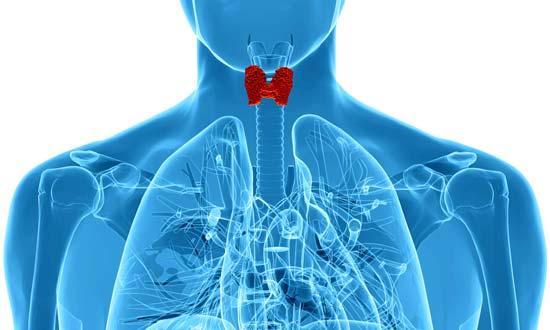

Dos ejemplos comunes son la demencia causada por deficiencia de vitamina B12 o tiroides hipoactiva (hipotiroidismo).

7. Enfermedad de la tiroides: Una producción excesiva de hormonas tiroideas (hipertiroidismo) es comúnmente causada por la enfermedad de Graves, mientras que una baja producción (hipotiroidismo) suele ser resultado de la tiroiditis de Hashimoto.

Ambos trastornos pueden causar síntomas parecidos a la demencia.

El hipertiroidismo: Para el diagnóstico del hipertiroidismo, los médicos usan un simple análisis de sangre que mide los niveles de las hormonas tiroideas.

La extirpación quirúrgica de la glándula tiroides o su destrucción con yodo radiactivo, generalmente, corrige los problemas cognitivos.

El hipotiroidismo: Este se diagnostica midiendo el nivel de la hormona estimulante de la tiroides que circula en la sangre.

Los médicos suelen recomendar el reemplazo de la hormona tiroidea, pero este tratamiento no siempre invierten la demencia.